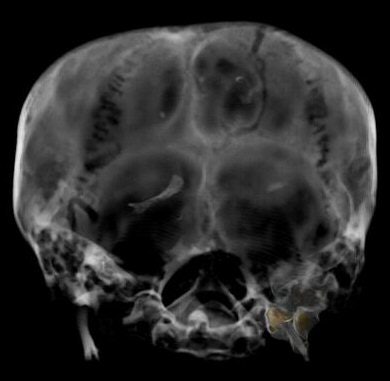

![]() |

| Image of bone fragment in the skull of King Tut. Image courtesy of Egypt's Supreme Council of Antiquities. |

The group was also able to dispel the theory that the young pharaoh was murdered from being struck on the head. "The team found no evidence for a blow to the back of the head, and no other indication of foul play," the researchers stated.

They did, however, find two loose bone fragments in the skull. But the team agreed that the bones could not have been caused by an injury before the king's death, as the fragments would have been stuck in the skull due to the embalming process. The bones matched a fractured cervical vertebra and foramen magnum, which may have been broken during the embalming process, or by Carter and his team after the mummy's discovery, according to the researchers.